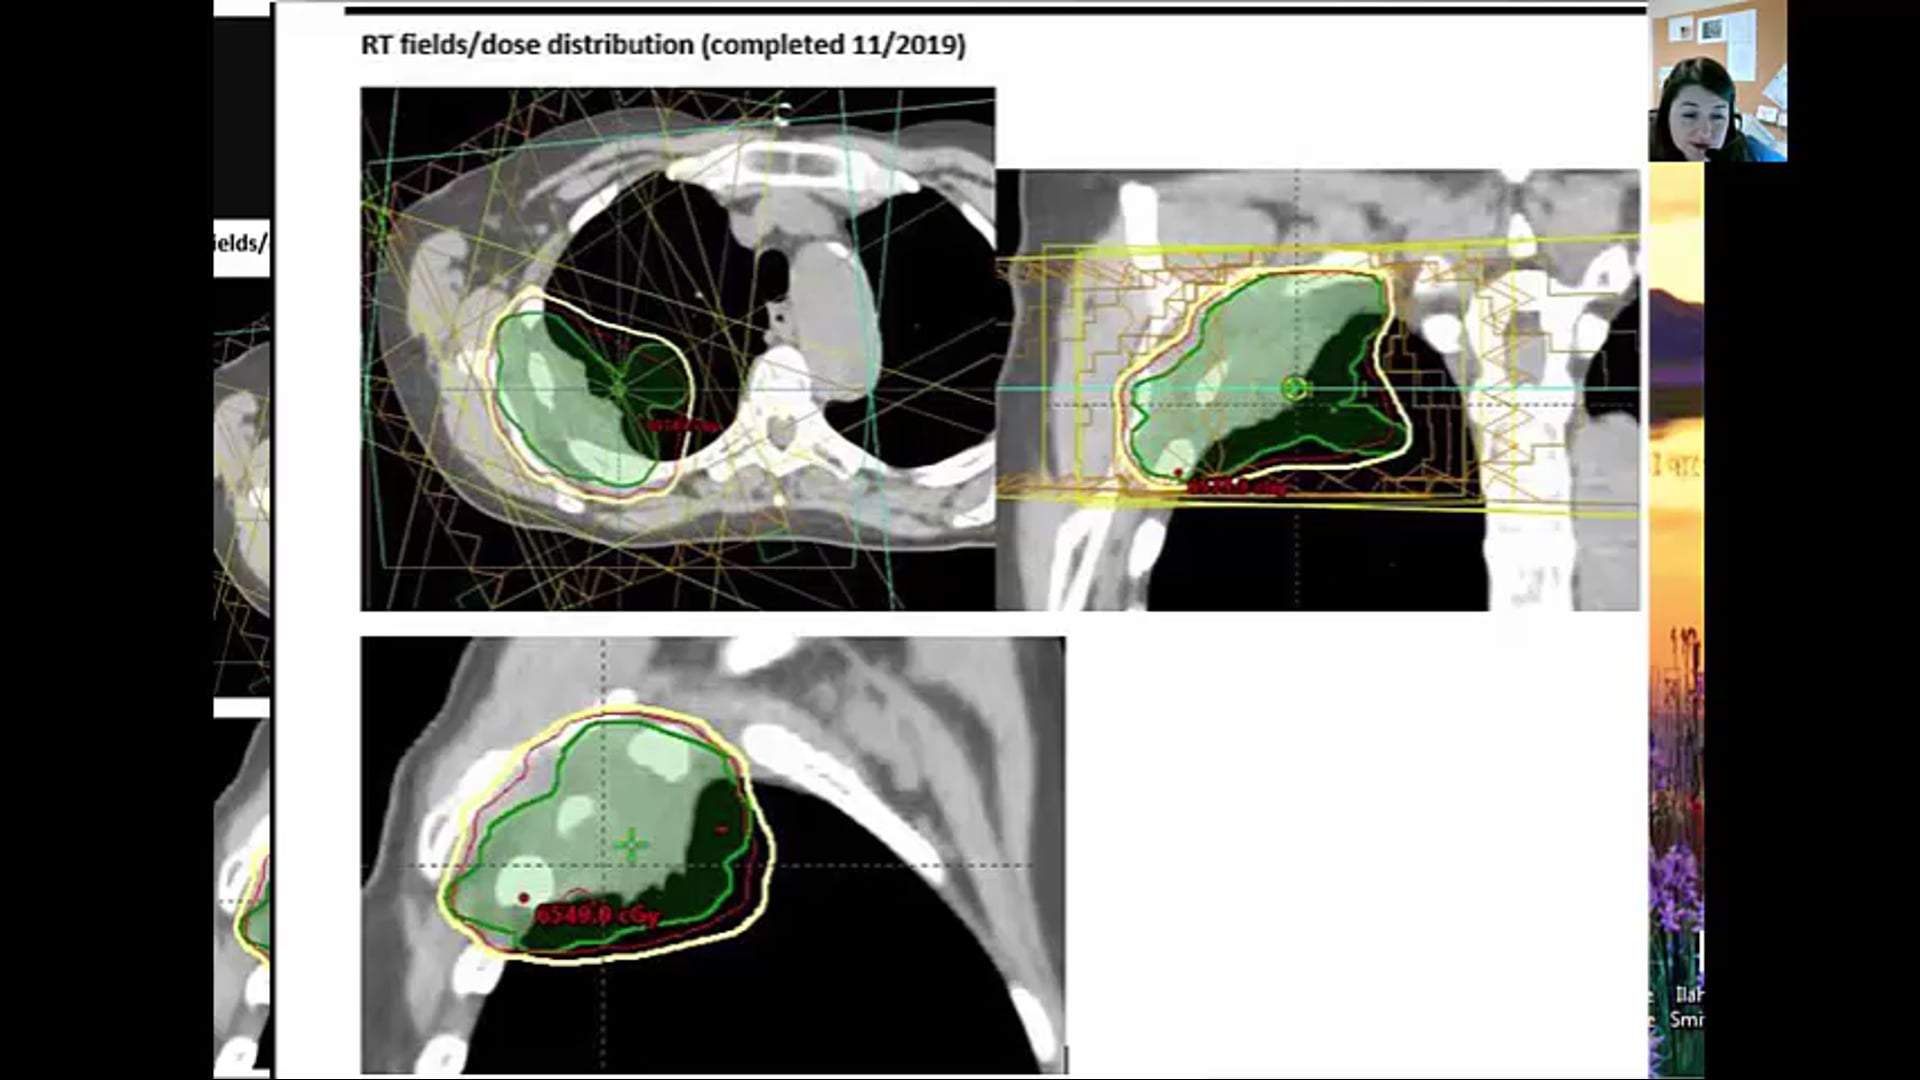

11/21/19 - Dr. Candice Johnstone - Radiation Oncology - Lung US

refused chemotherapy, tumor, dose-volume constraints, CORSAIR, 55Gy 20 regimen, SBRT, CTV, clinical target volume, fractionation